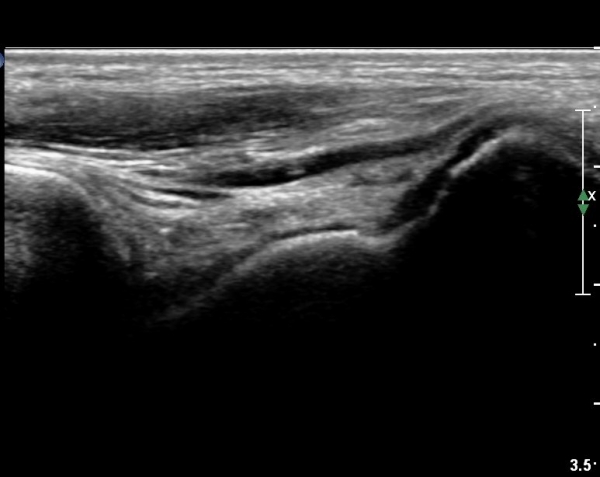

Á¾°ñ Àü¹æ µ¹±â(anterior process) °ñ±Ø°ú Ȱ¾×¸·¿° ¼Ò°ßÀ» º¸ÀÓ(»çÁø 3, 4).